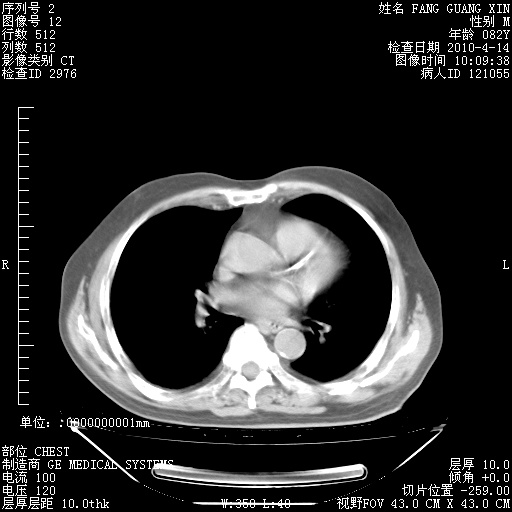

4月14日肺部CT